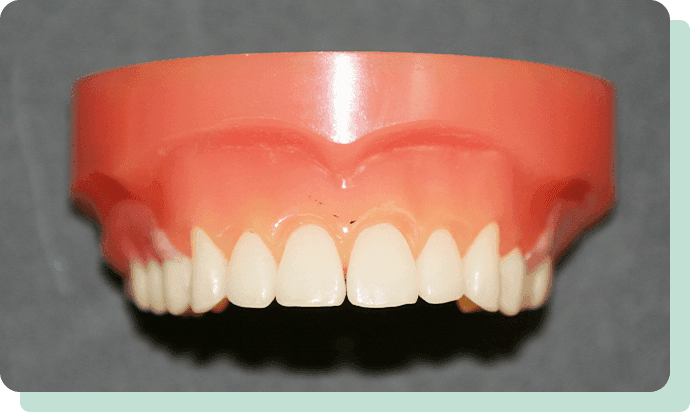

従来の入れ歯は、歯ぐきに触れる部分がプラスチック(レジン)もしくは金属でしたが、シリコンデンチャーでは歯ぐきに触れる部分に生体用シリコン(軟らかい素材)を使用。そのため、当然ながら軟らかい歯ぐきにやさしく、抜群のフィット感を得られます。

また、歯ぐきや残っている歯との間に隙間ができにくく、痛みの原因となる食べカスが入りにくいという利点も。

万一、歯ぐきの状態が変化して、入れ歯が合わなくなったとしても、バイオシリコンの部分だけの張替えも可能です。

参考模型